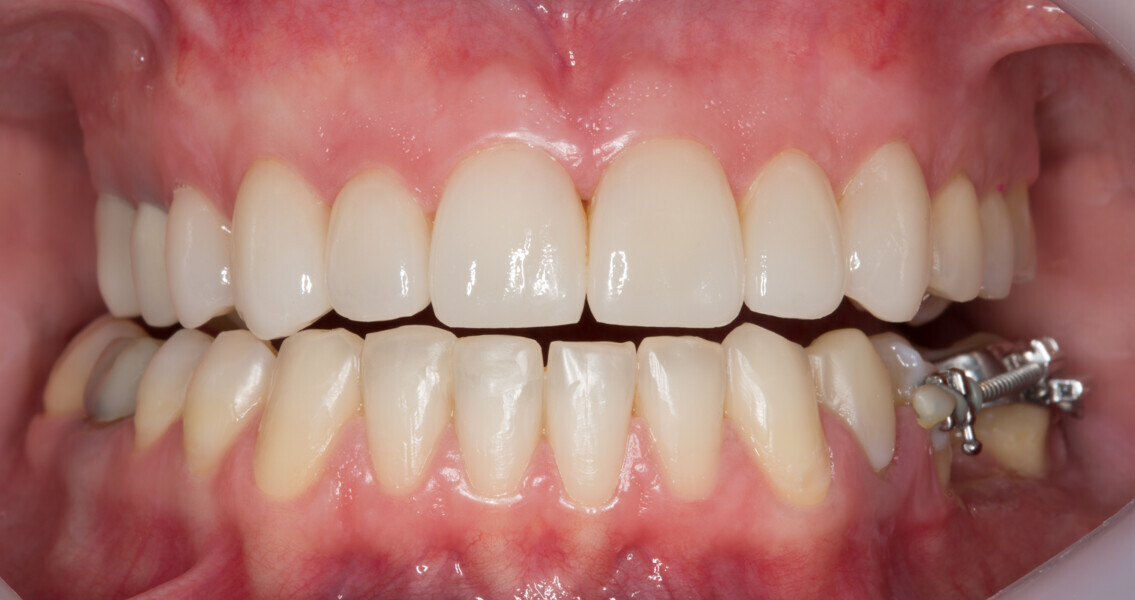

Fig. 1: Initial clinical situation.